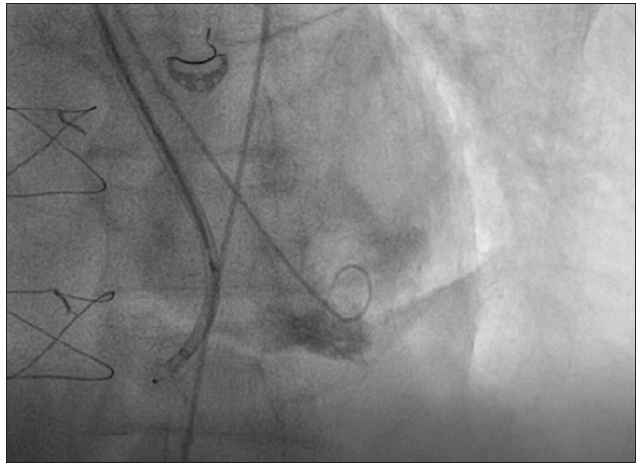

APPROACH OF THE MODERATOR

We performed transcatheter closure of the LV pseudoaneurysm with a 16-mm Amplatzer VSD occluder and transcatheter mitral valve repair with a MitraClip (Figure 1). The choice of this particular device and size were based on the CTA sizing. We inserted the deflectable 8.5-F Agilis sheath (Abbott) through the left brachial artery into the left ventricle (the length of the Agilis was too short for the femoral approach in this patient). We then inserted the 5-F pigtail catheter into the Agilis. The sheath was deflected to navigate toward the defect in left anterior oblique cranial projection. After we confirmed the tip of the pigtail was in the pseudoaneurysm, we proceeded with the closure. The deflectable sheath greatly improved the navigation. Because the severe mitral insufficiency persisted, we decided to perform the MitraClip procedure as a second stage. The procedure successfully reduced the regurgitation from severe to mild (Figure 2).